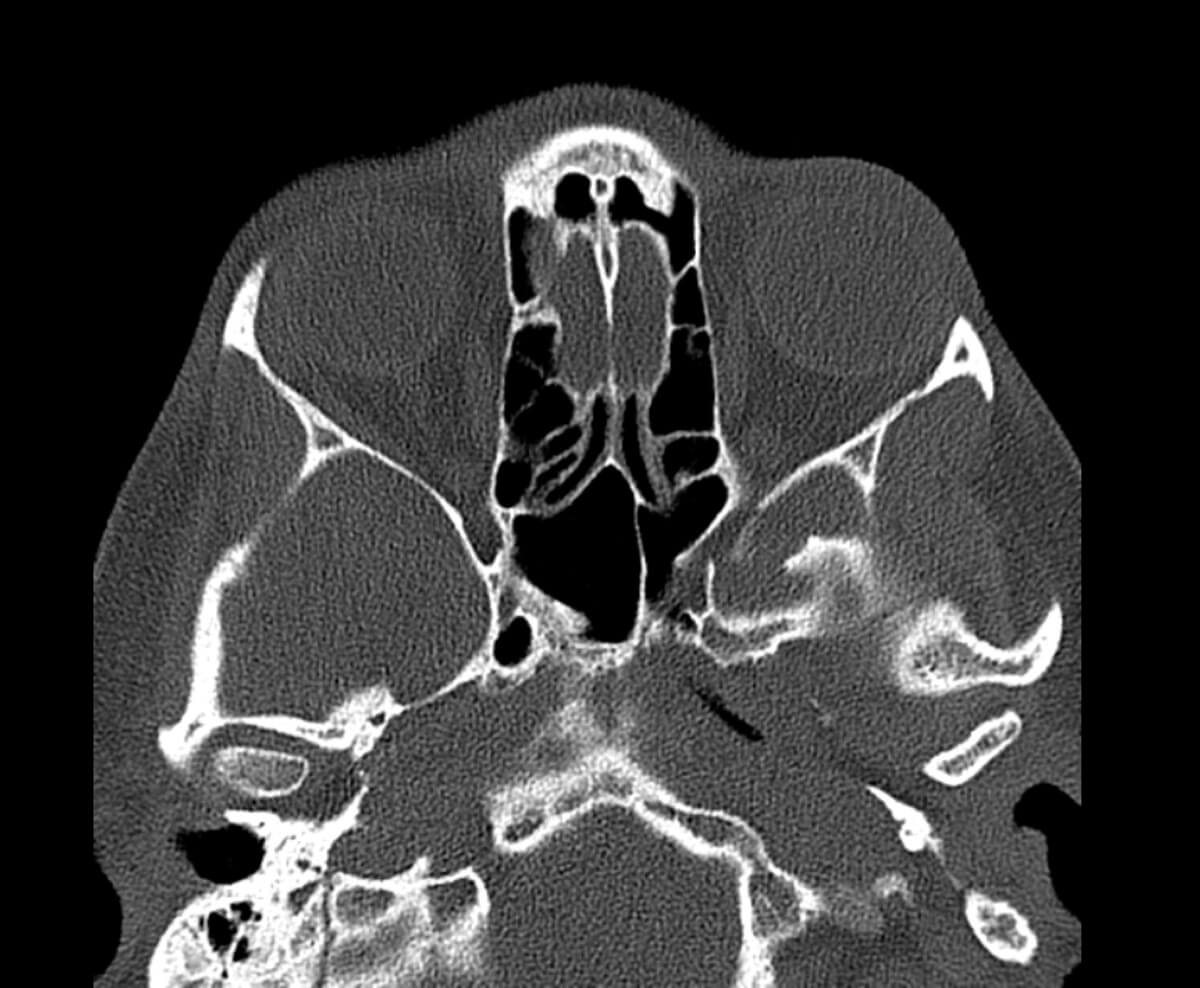

Figure 2b: CT facial bones, brain, sinuses without contrast - thin, bones.

Computed tomography (CT) imaging showed no acute intracranial abnormality with minimal periorbital haemorrhage without evidence of significant optic nerve compression. Despite this, clinical findings strongly indicated OCS, prompting the decision to proceed with an emergency LCC.